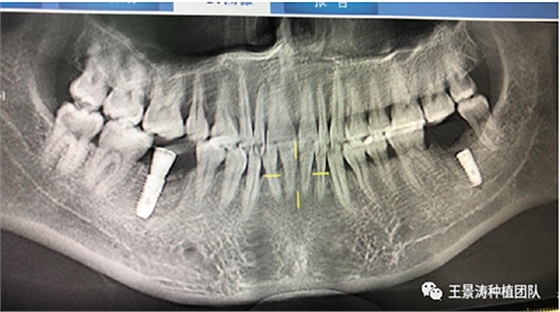

患者左側(cè)16慢性根尖周炎,17缺失。16根尖炎癥距上頜竇底較近,需內(nèi)提升,但是因?yàn)閮?nèi)提升后骨質(zhì)較薄所致植入深度過深,埋入式植入。17非埋入式種植。后期效果均可。